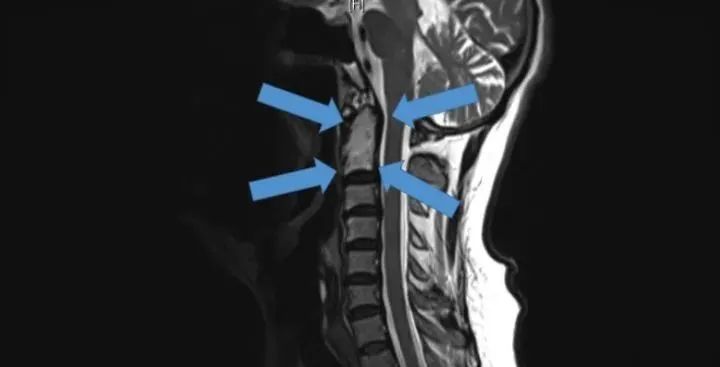

△2015年底,世界首例采用3D打印椎骨植入物

脊柱行業(yè)也是未來醫(yī)療器械市場,最新發(fā)展趨勢之一。通過3D打印技術(shù),來達(dá)到創(chuàng)新產(chǎn)品的目的,該技術(shù)可以促進(jìn)骨骼向內(nèi)生長,并改善植入物對脊柱骨的固定,縮短制造流程,提高患者滿意度,從而在某些情況下更具成本效益。

例如,Medtronic鈦金屬3D打印平臺(tái)——TiONIC技術(shù)。使用激光方法制造具有增強(qiáng)表面紋理的植入物。Artic-L是該公司使用TiONIC技術(shù)制造的第一款金屬植入物。可供外科醫(yī)生在脊柱手術(shù)中使用。還有K2M的Lamellar,同樣采用鈦制造3D脊柱植入物。使用金屬3D打印技術(shù)特有的優(yōu)勢之一,可實(shí)現(xiàn)曾經(jīng)被傳統(tǒng)制造技術(shù),認(rèn)為不切實(shí)際的結(jié)構(gòu)。